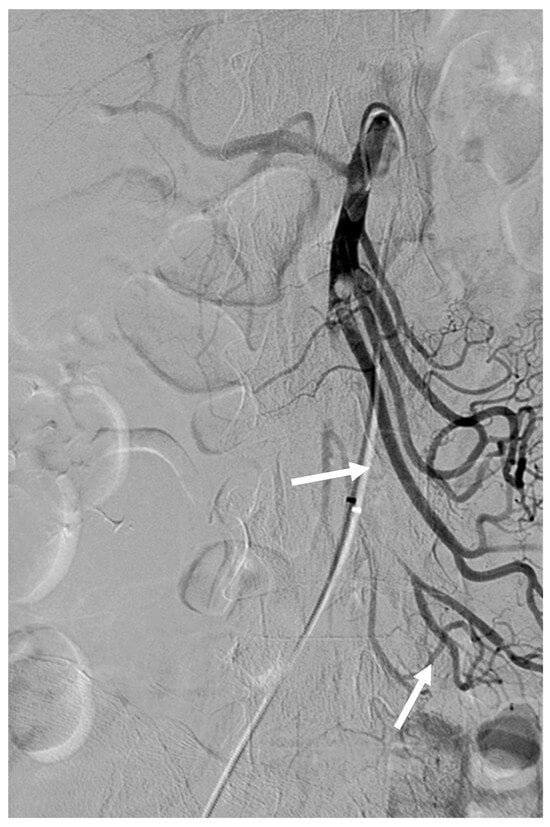

Figure 2. After thrombolysis using 2 mg of rtPA via RH catheter, angiography revealed partial recanalization of jejunal and ileal branches of the SMA (arrows).

After several attempts, we decided to change our plan of performing embolothrombectomy to thrombolysis using a 5 Fr RH catheter and microcatheter (Progreat Lambda, Terumo, Somerset, NJ, USA) with rtPA. We diluted 5 mg of rtPA in 25 mL of saline and 25 mL of contrast solution to prepare an rtPA solution. Subsequently, the SMA was selectively catheterized using a 5 Fr RH catheter. rtPA (2 mg; 20 mL of rtPA solution) was carefully injected (1 mg per 10 min) through the RH catheter. After thrombolysis, angiography revealed partial recanalization of the proximal SMA and its jejunal and ileal branches (Figure 2). Segmental SMA occlusion with sluggish jejunal flow remained, and no visible colic flow was observed.